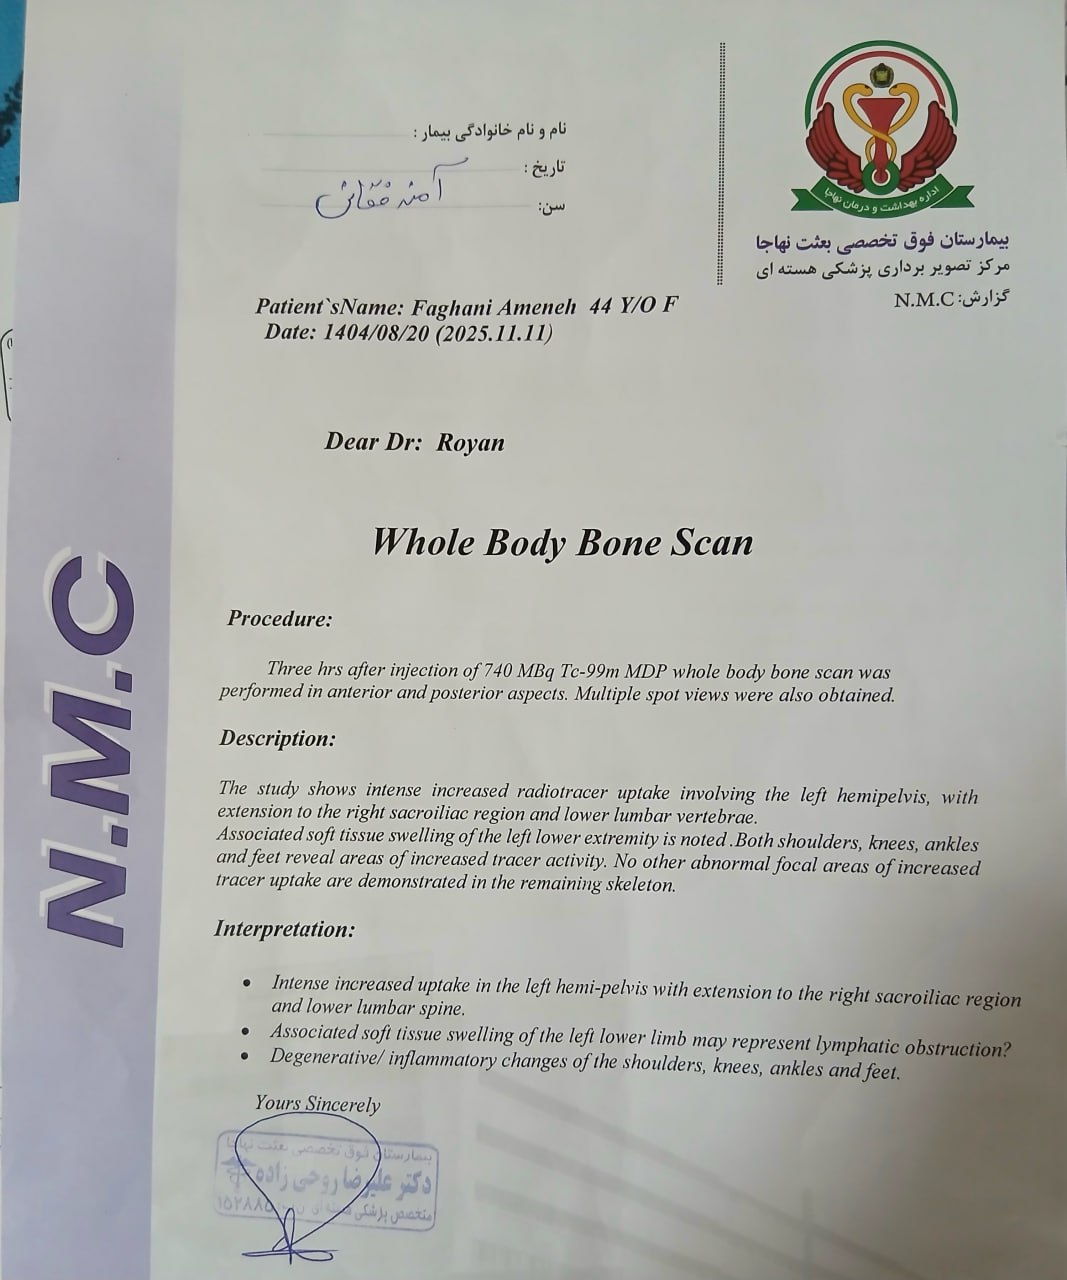

در بررسیهای تصویربرداری (MRI)،در تاریخ 24.7 ، تودهای با تشخیص کندروسارکوما همراه با DVT گزارش شده است. بیمار سابقه درد لگن داشته که شدت آن در حال حاضر نسبت به گذشته کاهش یافته است. به گفته بیمار، حجم توده در ابتدا در حدود اندازه یک تخممرغ بوده که در حال حاضر کاهش یافته است. همچنین تورم اندام تحتانی در حال حاضر نسبت به قبل کمتر شده است.

مراجعه کرده است. پس از بررسی های انجام شده در MRI انجام شده توده با درگیری مفصل ساکروایلیاک چپ و DVT؛ ابتدا تحت درمان DVT قرار گرفته است و سپس جهت پیگیری تومور رویت شده تحت بیوپسی قرار گرفته است و با تشخیص کندروسارکوما به این مرکز مراجعه کرده است و تحت کموتراپی و رادیوتراپی قرار گرفته و سایز تومور کاهش یافته است.